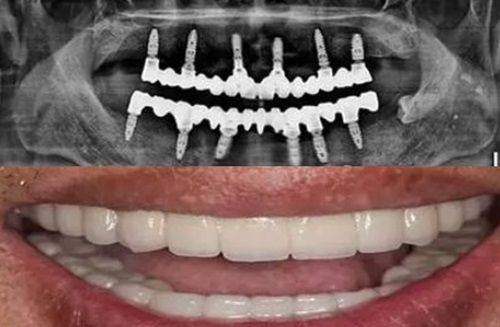

再如北京佳美口腔门诊部的佳美即刻种植牙,术中通过数字化影像扫描定位,种植牙定位精细、操作快捷省时、成功几率高。北京中腾口腔医院在种植牙技术上也与国内外接轨,相信在收费合理的情况下,能为患者提供不逊色于其他医院的服务。

而北京中腾口腔医院在这样的市场环境下,凭借专精的医疗团队、与国内外接轨的技术交流以及严格的消毒隔离制度,能为患者提供安心、可靠的种植牙服务。虽然我们不清楚其具体的种植牙收费,但从其整体实力和行业规范来看,有望在确保质量的前提下,给出相对合理的价格。